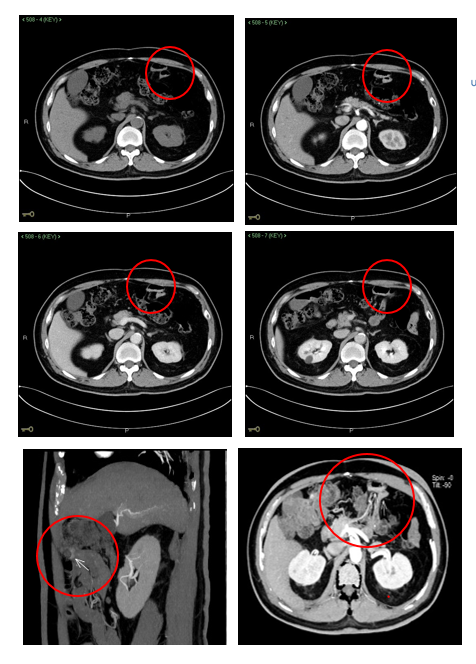

在随后的阅片过程中,陈大夫仔细地对腹部各脏器、各段肠管及血管逐一排查,终于发现了引起了患者身体不适的元凶:

在胃空肠吻合口的输出段近端肠腔内有少量稍高密度液体积聚,多期动态增强图像显示该处液体量及密度具有随时间发生细微变化的特点,符合消化道活动性出血影像表现。

CT 多期增强图像清晰显示对比剂积聚